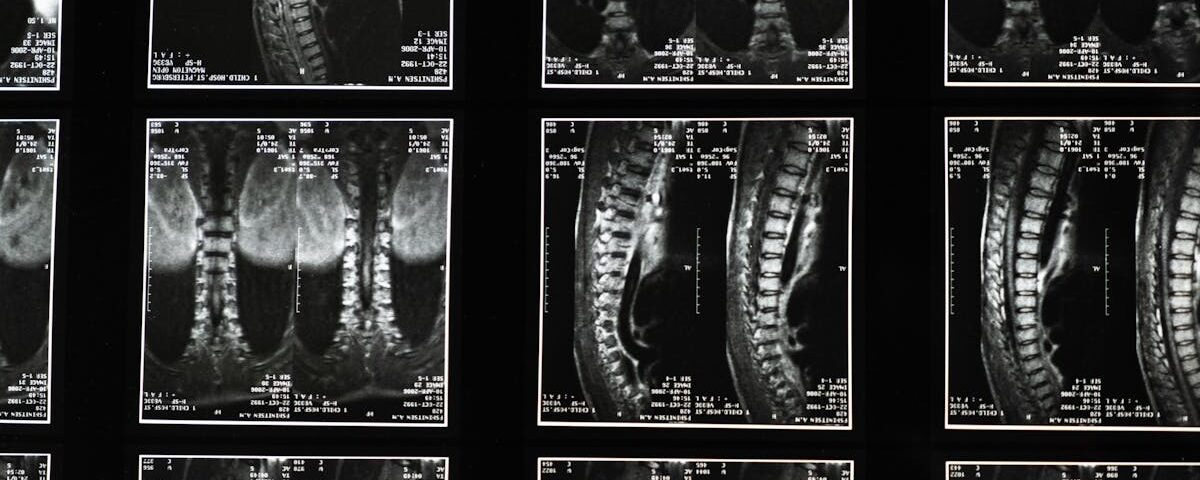

Quels examens permettent de diagnostiquer un bombement discal?

Une IRM ou une radiographie sont les outils les plus couramment utilisés pour diagnostiquer un bombement discal.